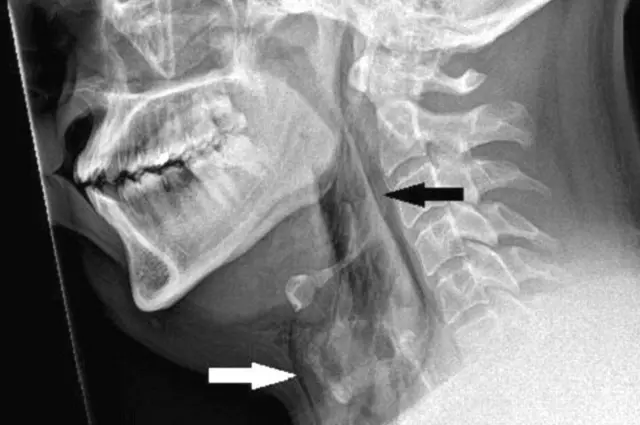

स्कैन में पता चला कि छींक रोकने के कारण उनकी श्वासनली में 2 मिलीमीटर तक का जख्म बन गया.

डंडी यूनिवर्सिटी के डॉक्टरों का कहना है कि छींक आते वक्त अगर व्यक्ति अपने मुंह और नाक को बंद कर दे तो इस कारण श्वासनली में ऊपर के हिस्से का दवाब 20 गुना तक बढ़ सकता है.

इमेज स्रोत, BMJ